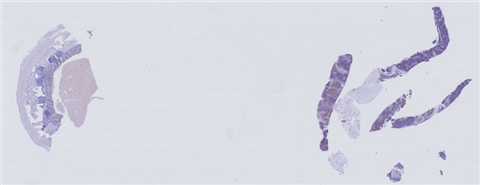

患者详情: 因“发现颈部肿物2天入院”,入院检查:颈前部居中可触及大小约3.0cm*2.0cm*1.0cm肿物,边界清,稍固定,无压痛,不随吞咽上下移动,与皮肤无粘连,表面皮肤无泛红。 颈部+胸部CT:胸骨上窝可见一个类圆形软组织影,约35mm*29mm*22mm,密度均匀,CT值约21Hu,边界清,周围血管受压移位,增强扫描病灶欠均匀强化,CT值56Hu。胸廓对称无畸形,双肺、心膈未见明显异常。 病理肉眼所见:直径0.1cm,长1.0cm-1.2cm灰白色线条样组织4条。